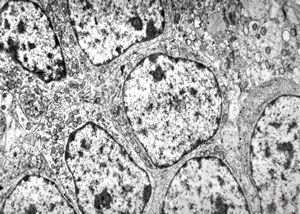

F,32y. | transversally sectioned skeletal muscle cell

mouse skeletal muscle cell - transversal section